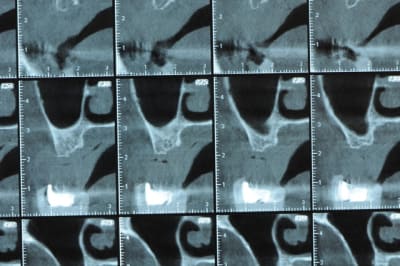

un cas pour PXAV.

ça c'est le domaine de pxav.

qu'en penses tu ?

j'ai besoin de 4 implants au maxillaire pour faire tenir son complet.

dans la zone postérieur, pas de problème, mais devant, c'est une autre histoire.

Non sans décorner, superbe cas de début pour expansion, bone splitting et tout et tout.

la corticale a l'air tiptop, par contre en cas d'expansion il faut eventuellemnt augmenter le nombre d'implant à 6 pour compenser eventuellement le manque d'epaisseur 'avis personnel)

Je suis sceptique sur la gestion de ce cas par bone splitting puisqu'il met parait très difficile d'obtenir un volume osseux peri-implantaire crestal suffisant et satisfaisant.

+1 Olive, ce serait à mon avis plus prédictible avec des greffes. Je doute qu'on puisse obtenir suffisamment d'os en vestibulaire et en palatin des implants en splittant une crête aussi fine.

De ce que j’ai vu du cas de D57 c’est me semble t il un magnifique cas d’expansion, ce qui ne veut pas dire rien d’autre

Une petite étude de ton cas D57

Sous réserves bien sur de voir l’animal en vrai

Les zones exploitables radiologiquement parlant:

Coupes implant

2,3 40100

4,96 35130 avec sinus lift mais difficile

5,25 35150

6,02 35130

6,78 35115 après réduction de hauteur de crête

7,26 35115 après réduction de hauteur de crête

8,51 35150

10,43 40115 ou 50115

11,10 40115

Ce qui nous fait 9 implants possible évidement avec un comblement de sinus on augmenterait encore les zones implantable mais ce n’est pas le but recherché, avec 8 (4+4) il doit être possible de faire une belle barre support de complet